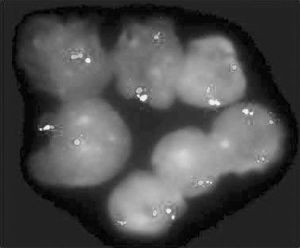

CML具有特徵性的費城染色體(Philadelphia chromosome,ph)t(9;22)(q34.1;q11.21)使9號染色體上的原癌基因c-abl與22號染色體上的bcr基因融合形成bcr-abl嵌合基因是惡性克隆的基因標誌。在CML患者的粒系、紅系、巨核系以及淋巴系均帶有此標誌,表明病變發生在造血幹細胞水平。該嵌合基因轉錄-8.5Kb的mRNA,編碼-融合蛋白-P210 bcr/abl,該融合蛋白通過抑制白血病細胞的凋亡延遲而在CML發病中起重要的作用。由於是多能造血幹細胞的惡性增殖,故粒系、紅系、巨核系等多系受累,急變期可轉變為淋巴細胞白血病。

約85%以上的CML患兒存在Ph1染色體即t(9;22)。對Ph1染色體陰性者,用分子生物學技術又可分為有bcr重組(Ph-bcr+CML)和無bcr重組(Ph-ber-CML)兩亞型前者臨床症狀與Ph1染色體陽性者類似,後者臨床症狀不典型。